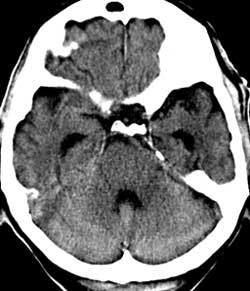

Рис. 7. Влияние коллимации и толщины среза на качество изображений на примере исследования головного мозга. Во всех случаях коллимация 1 мм. (Слева) Реконструированная толщина среза 1 мм. (В центре) Толщина среза 4 мм. (Справа) Толщина среза 8 мм. На изображении (Слева) на область варолиевого моста накладываются артефакты от пирамиды левой височной кости. На изображениях (В центре) и (Справа) они практически отсутствуют - эффект усреднения, однако при толщине среза 8 мм (Справа) нечетко визуализируется ликворное пространство над правой гемисферой мозжечка по той же причине. Толщина среза 4 мм в данном случае оптимальна.